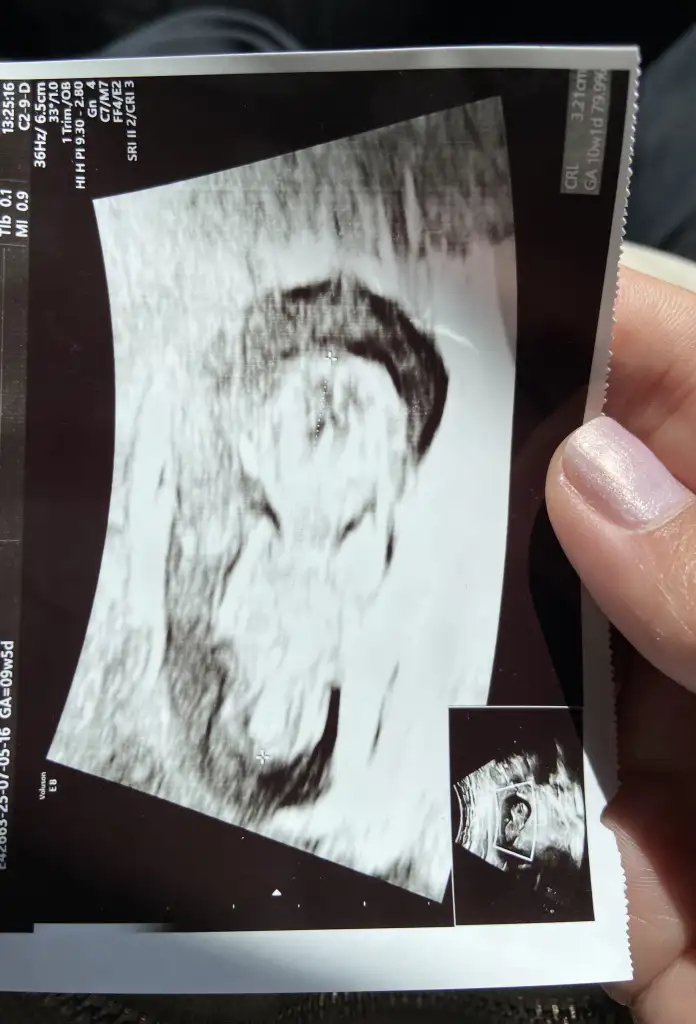

Maşallah gruba bir erko daha eklendiArkadaşlar bugün kontrolüm vardı, çok şükür her şey yolunda tam 14. Haftamdayım veeeee cinsiyeti öğrendikben hissetmiştim biliyordum zaten erkekmiş

Benim crl de hesapladığım hafta yazıyor ama doktor bebek önde dedi. Anlamadım. Çok merak ettim şimdi :) Ama doğru bilgi verilmemesi yanlışBenimde öyle sözde özel ama özel demeye bin şahit ister Oyüzden memlekete gitmek istiyorum ultrason cihazları çok kötü buranın canım aslında sen sormadan hastasını söyler genelde doktor ama birde verdiği fotoğrafda da yazıyor hem crl hemde haftası bu gidişinde dikkat et görürsün inşallah sağlıklı olsunda haftası boyutu değişir bazen herkeste hemen hemen böyle

Çin takvimi ne diyordu? Hayırlı olsun bu aradaArkadaşlar bugün kontrolüm vardı, çok şükür her şey yolunda tam 14. Haftamdayım veeeee cinsiyeti öğrendikben hissetmiştim biliyordum zaten erkekmiş